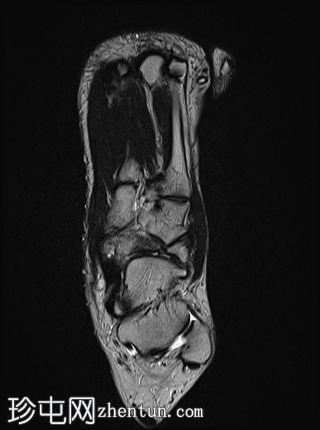

轴向

T1

舟骨呈二分状,分为两个骨块——较大的内侧骨块和较小的外侧骨块。

内侧骨折块外侧面呈“逗号状”,舟骨相对于距骨头轻微向内移位。

外侧骨折块及其外侧均呈斑片状T1低信号和PD FS高信号,并伴有硬化和微小囊肿,提示软骨联合/纤维界面存在慢性应激反应或退行性改变,可能伴有缺血性坏死。

双分舟骨区域外未见急性骨折线或骨髓水肿。

周围跗骨和关节未见明显异常。

未见明显软组织异常或关节积液。